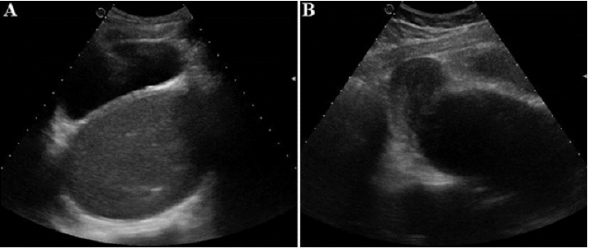

In case of diagnostic doubt, ultrasound may be helpful in showing the hematocolpos as a midline, retrovesical fluid-tone image containing a few heterogeneous echoes. This collection is surmounted by the communicating uterine cavity, which is often small, dilated by fluid content in the event of hematometry [23,24]. Hematosalpinx or peritoneal effusion can be found [24,25]. The ultrasound examination also analyzes uterine malformations. Renal agenesis is systematically sought, especially in cases of genital duplication [5]. Ultrasound may also show ureteropyelocalicular dilation in the event of compression of the urinary tract by hematocolpos [26,27]. In our patient, an abdominopelvic ultrasound was performed and revealed an intra-vaginal fluid collection in favor of hematocolpos. The antenatal ultrasound at 20 weeks of amenorrhea shows a collection image in the small pelvis, behind the bladder, but this mass can have several etiologies (anterior sacrococcygeal tumor, anterior sacral meningocele, ovarian cyst) [28,29]. Around 24 weeks of amenorrhea, following the development that the diagnosis asserts, the anterior sacral meningocele and the sacrococcygeal teratoma will develop towards the caudal region, while the ovarian cyst and hydrocolpos develop towards the cranial region [29]. The sex will be visible on this date, and the shape of the collection that will evoke the diagnosis.

Figure 3:

A. Axial Suprapubic ultrasound: presence of a retrovesical, median, hypoechoic fluid formation containing a fine echogenic stippling

B. Sagittal section: the collection communicates at the top with the uterine cavity which is not distended.